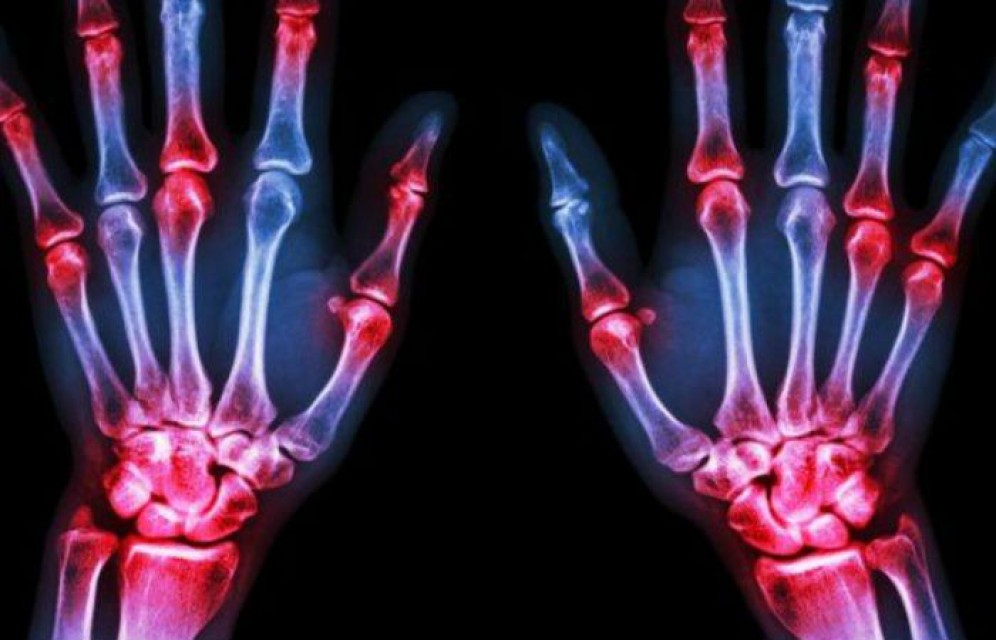

Новозеландские ученые представили первый в мире рентгеновский аппарат, способный делать трехмерные цветные снимки, передает ТАСС.

Как сообщает на своем сайте Европейская организация ядерных исследований (ЦЕРН), уникальность прибора обеспечивается за счет технологии, разработанной для Большого адронного коллайдера (БАК).

Отмечается, что ученые из новозеландских университетов Кентербери и Отаго около десяти лет совершенствовали оригинальный чип Medpix, предназначенный изначально для наблюдения за экспериментами на коллайдере, и адаптировали его под медицинские нужды. Вместе с 20 исследовательскими институтами отец и сын - профессора Фил и Энтони Батлеры - создали третье поколение чипа, который позволяет получить картинку с большим разрешением и высокой точностью прорисовки деталей. После успешных испытаний основанная ими компания MARS Bioimaging заключила лицензионное соглашение с ЦЕРН на использование этой технологии в коммерческой версии аппарата.

Уникальность разработки заключается в том, что она позволяет делать снимки, на которых отображается сразу несколько видов тканей, а также выявлять признаки заболеваний. Среди опубликованных компанией снимков есть, например, изображение запястья, на котором можно рассмотреть как костную ткань, так и мышцы.

Отмечается, что пользователи могут получить доступ как к снимкам, реконструированным при помощи заложенных в аппарат алгоритмов, так и к исходным данным, которые они могут обработать по собственной методике. Кроме того, производитель заявляет о низком уровне облучения, что должно упростить задачу врачей во время длительных исследований и позволит делать больше снимков без ущерба для здоровья.

До недавнего времени исследователи использовали экспериментальный сканер для диагностики раковых опухолей, состояния костей и суставов, а также сердечно-сосудистых заболеваний. "Первые перспективные результаты этих исследований показывают, что использование спектрографии в повседневной медицинской работе позволит ставить более точный диагноз", - заявил Энтони Батлер.

Ожидается, что уже в ближайшие месяцы пациенты ревматологических и ортопедических отделений новозеландских клиник получат возможность пройти обследование на данном аппарате, сообщается на сайте ЦЕРН.